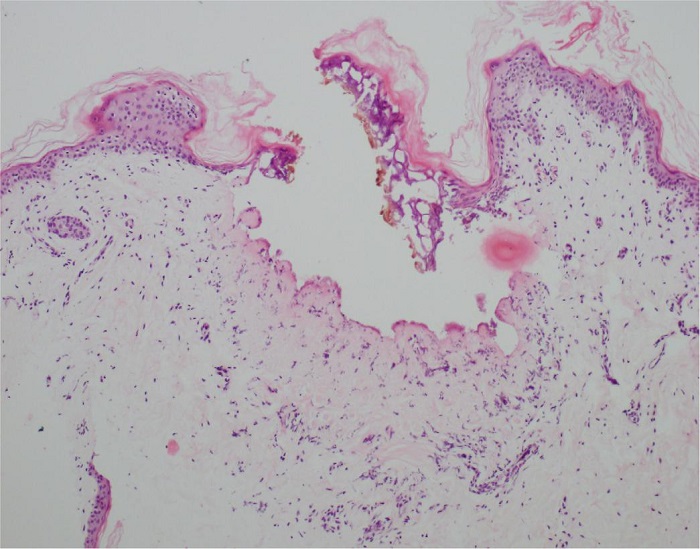

Na área B (Figura 2), observou-se a presença de duas pequenas áreas de figuração de dimensões semelhantes. Uma delas, em localização excêntrica, foi mais bem observada, medindo de 0,13 a 0,15 mm de diâmetro e 0,5 mm de profundidade, sem considerar a epiderme. Na derme papilar circundante, há uma leve redução na quantidade de tecido elástico.